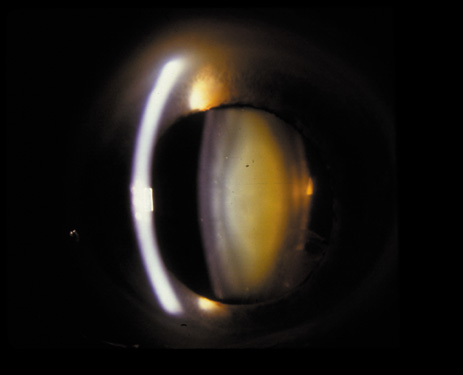

PSC may also result from irradiation or steroid ingestion, or it may be associated with diabetes, high myopia,37–41 retinal degeneration (e.g., retinitis pigmentosa),42,43 and gyrate atrophy.44,45 In some cases, the PSC eventually may be pushed to the cortex as new fibers are laid down and the offending agent is no longer present (Fig. 16A and B).

Fig. 16. A: Scheimpflug slit image of two types of PSCs (steroid-induced and gyrate atrophy-related) showing the positions of the opacities. B: Densitometry profiles showing the position of the gyrate atrophy-related PSC in comparison with the steroid-induced PSC. These suggest that the PSC migrates anteriorly as the newly laid down fibers push the PSC deeper into the cortex.45